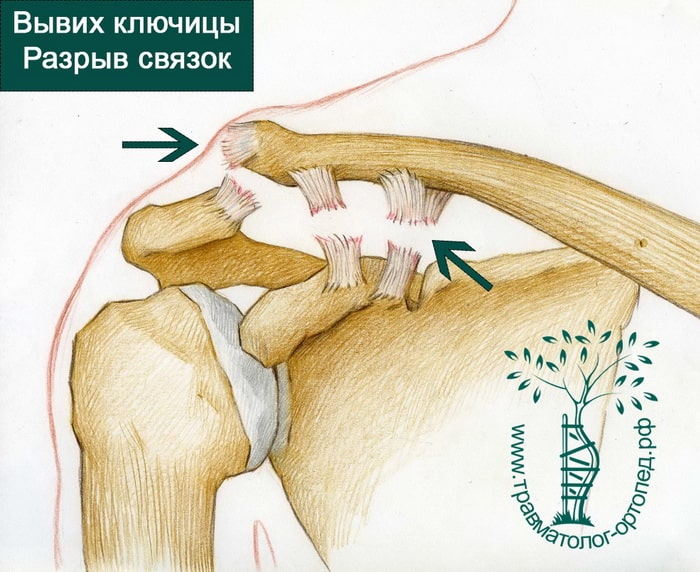

Вывихи и переломы ключицы презентация - 85 фото